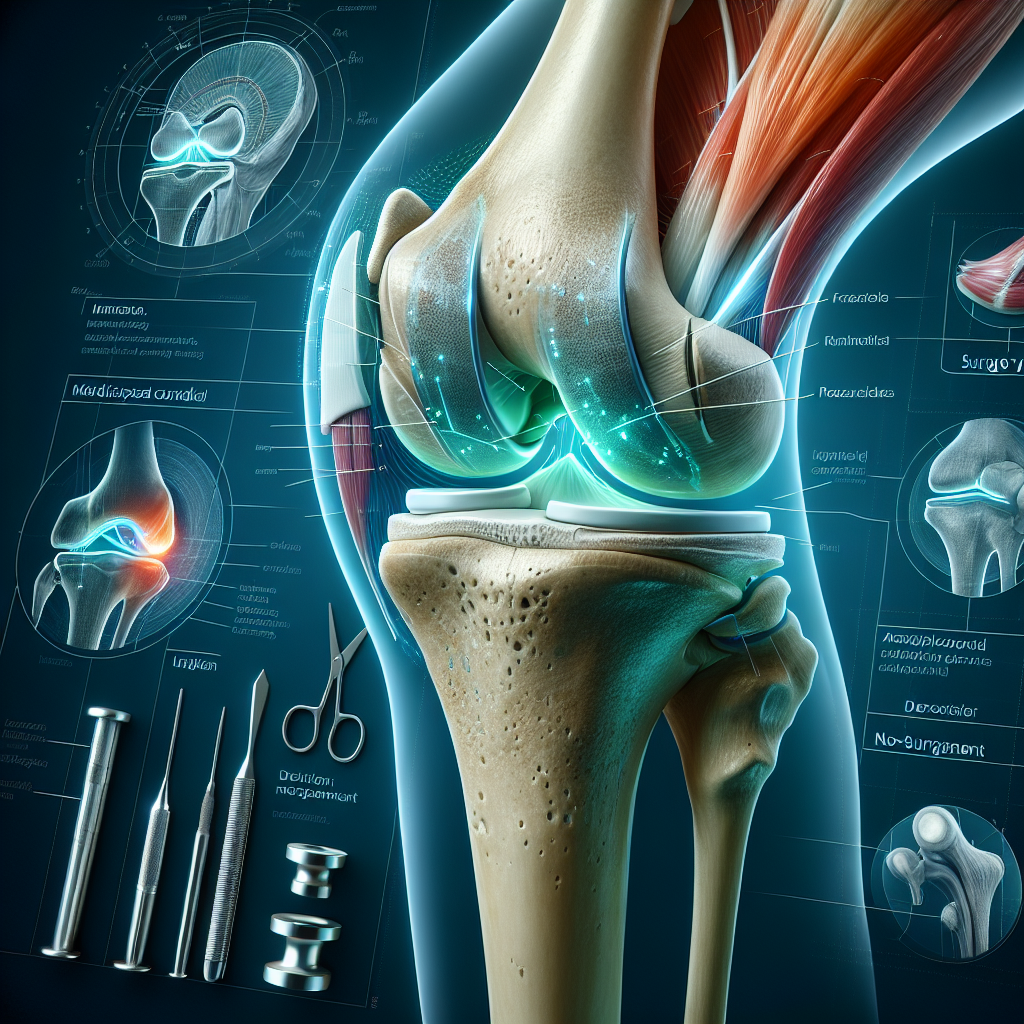

The medial femoral condyle, located at the end of the femur bone closest to the midline of your body, is a critical component of knee joint stability and function. When this structure suffers a fracture, particularly a minimally displaced one, it brings forth a cascade of considerations that both patients and orthopedic specialists must navigate.

The primary concern with a medial femoral condyle fracture is ensuring the proper alignment of the articular cartilage. Misalignment can lead to step-offs, which jeopardize joint function and increase the risk of premature arthritis due to uneven wear on the cartilage.

Surgery is frequently necessary to realign the bone correctly. A plate and screw configuration is commonly utilized to hold the fracture in place securely. This method ensures that the bone heals in its optimal position, preserving the knee’s function and minimizing the risk of future complications.